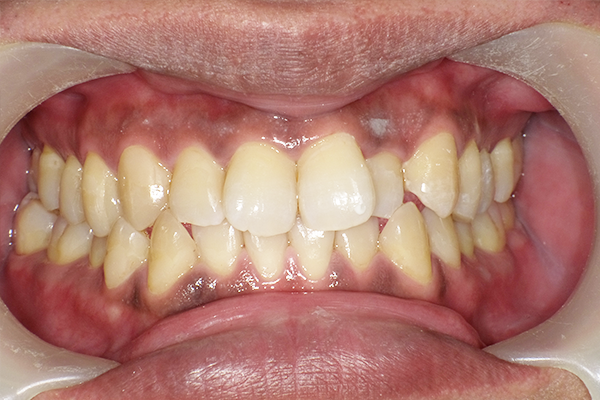

ホームホワイトニングスターターキット(27,500円(税込))+追加シリンジ4本セット(8,800円(税込))※2020年時点

主訴 歯の色が気になると来院。

全体クリーニング後、ご自宅でできるホームホワイトニングセット27,500円(税込)を購入。

2週間後、もう少し白くしたいとのことで追加で液を購入し、さらに2週間後希望の白さに近づけた。途中しみる症状が少しあったが落ち着いた。

治療期間:1か月

副作用・リスク:一時的に知覚過敏の症状が出る可能性あり